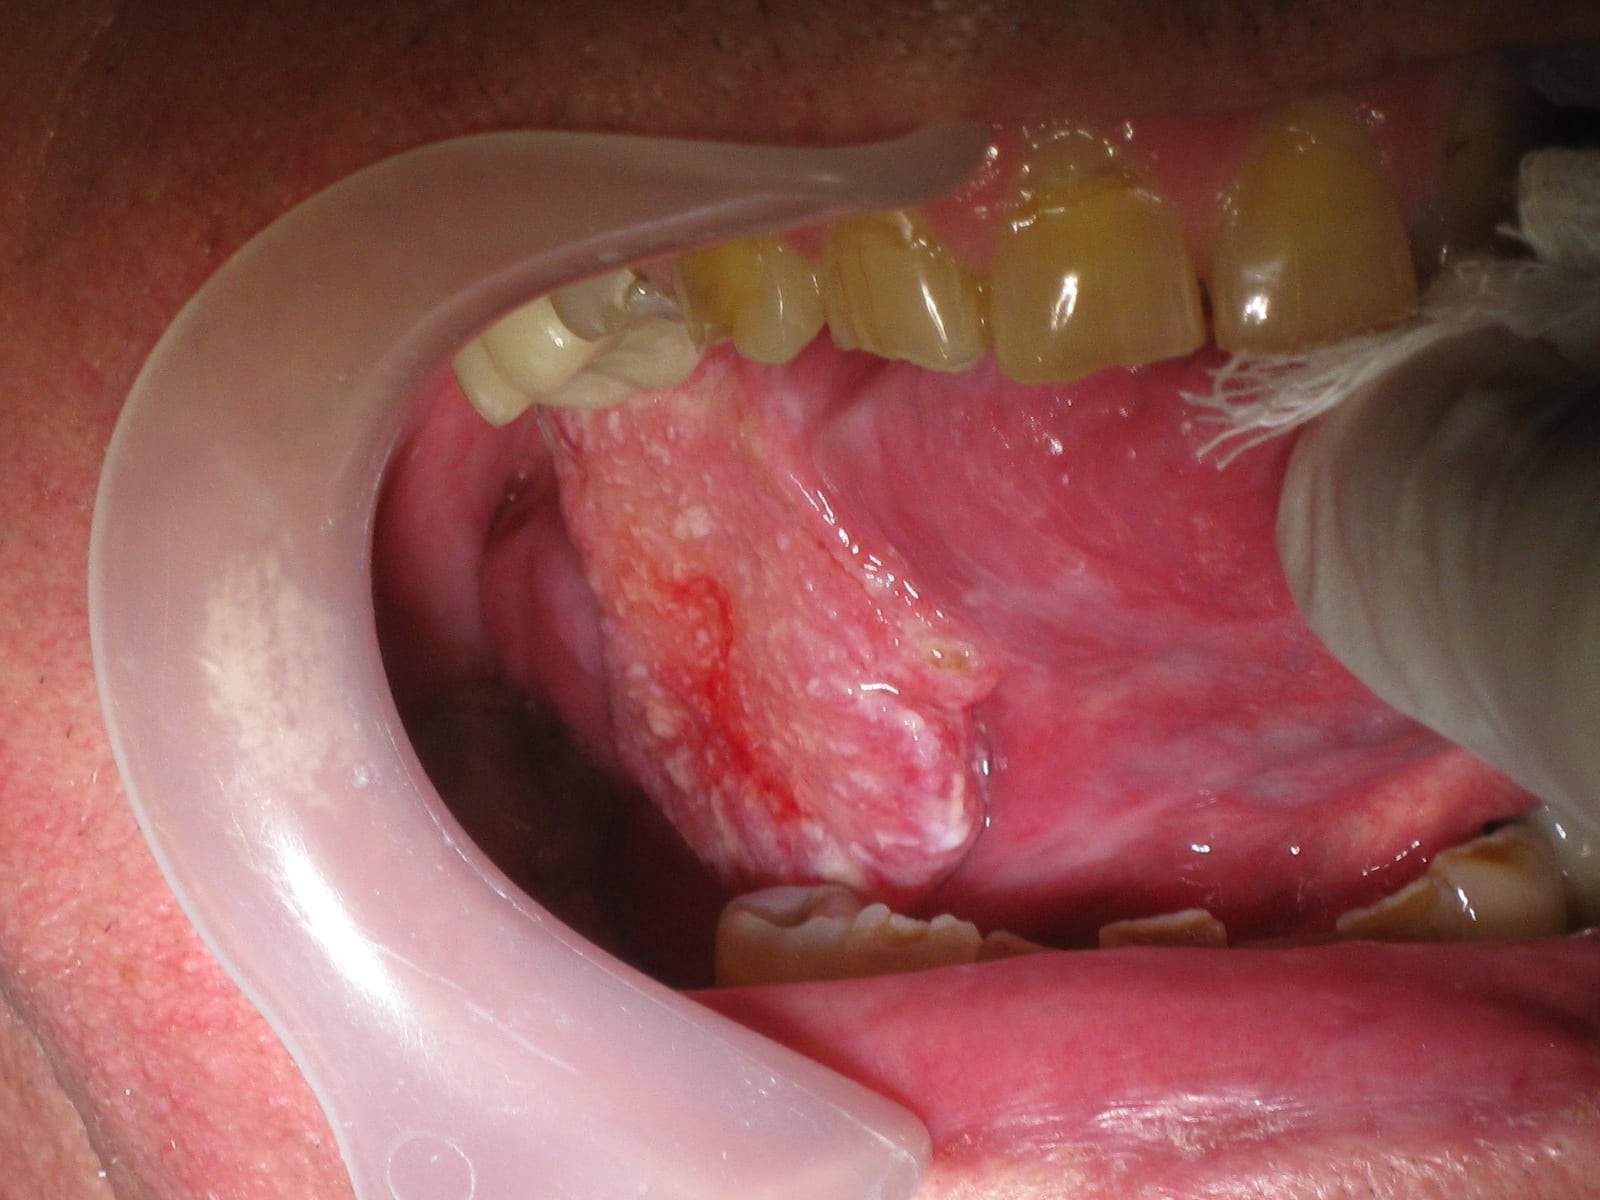

Deux patients hier matin, et le deuxième vient pour ''une lesion sur la langue qui commence a faire mal, gene la mastication et traîne depuis 3 semaines'','' mon docteur a jete un œil mais a voulu que je la montre a un dentiste''.

Mouais... J'ai très peur que ce ne soit pas du tout un aphte du a une irritation comme l’espérait le patient...

75 ans, ancien fumeur, consommateur régulier d'alcool, localisation sur le bord lateral de la langue, consistence ferme...

J'ai pris RV moi meme pour que le patient soit vu ASAP par le oral surgeon de la ville, mais je ne m'attends pas a de bonnes nouvelles...

Le patient a vu le oral surgeon ce matin, lequel m'a appele ensuite. La biopsie part ce jour, mais c'est très vraisemblablement un Squamous Cell Carcinoma m'a t-il dit.

Effectivement ça a l’air d’être un cas d’ecole de carcinome epidermoide.